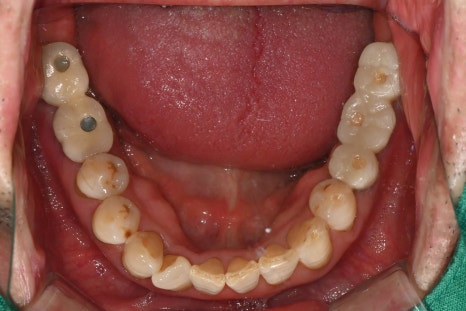

초진 내원당시

이번 케이스는 68세 남성 환자로, 잇몸이 심하게

붓고 통증이 발생한 상태에서 내원하셨습니다.

기존에 약을 복용하셨지만 증상이 호전되지 않았고,

어금니 부위의 통증이 점점 심해지는 상태였습니다.

검사 결과 어금니 주변 잇몸 내부에 고름이 형성된

치주농양 상태였으며, 뿌리 주변 뼈가 손상된 상태가

확인되었습니다.

어금니 발치와 임플란트 식립

염증이 심한 어금니는 발치가 필요하였으며,

발치와 동시에 임플란트 식립이 진행되었습니다.